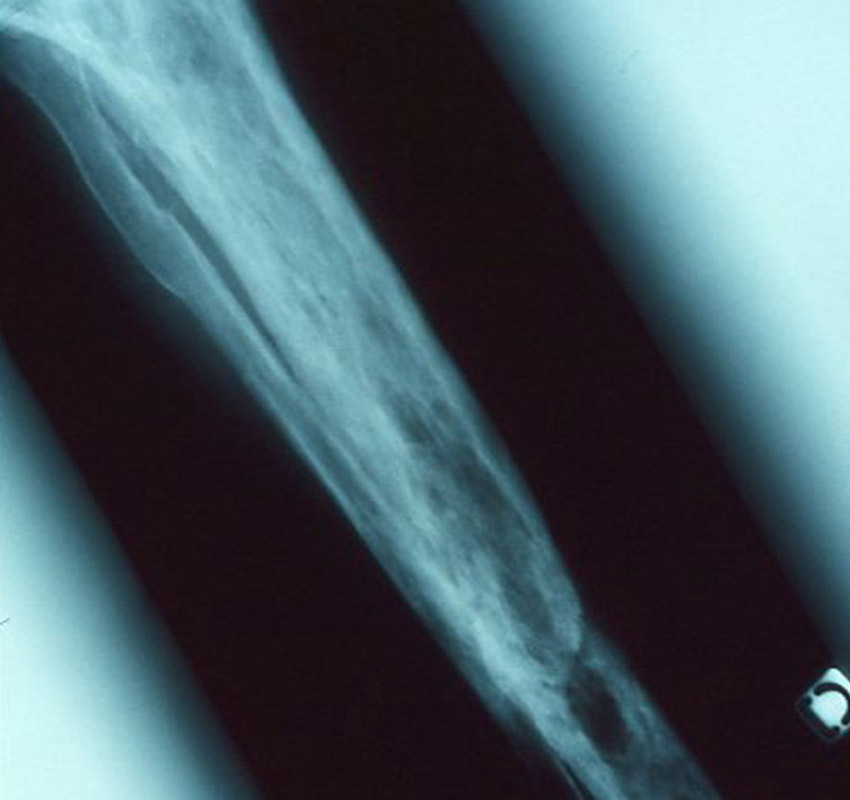

Il s’agit d’une maladie de Paget du tibia.

La maladie osseuse de Paget est une ostéopathie focalisée qui atteint soit plusieurs os (formes polyostotiques les plus fréquentes), soit un seul (formes monostotiques). Elle se caractérise par un dysfonctionnement des ostéoclastes et une augmentation de la résorption osseuse avec, secondairement, une augmentation de la formation osseuse ; ce remaniement excessif et anarchique du tissu osseux désorganise la structure et la morphologie des pièces osseuses touchées, qui se déforment, s’hypertrophient (pouvant ainsi comprimer des structures avoisinantes) et se fragilisent.